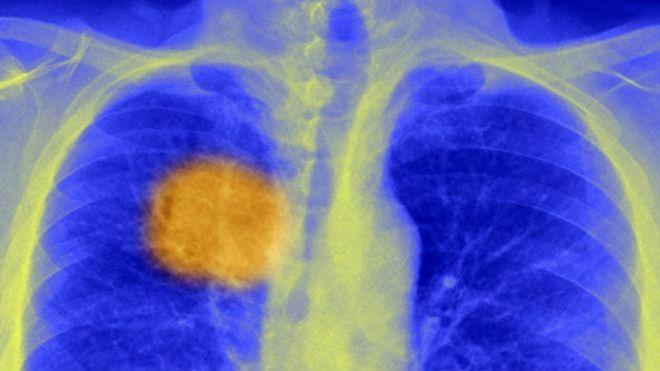

Иммунную систему привлекали для борьбы с онкозаболеваниями и раньше, но в основном все известные вакцины против рака оказались неэффективными. Ученые из Университетского колледжа объясняют это тем, что защитные механизмы организма направлялись на неверные цели. Дело в том, что раковая опухоль — это не единственное, равномерное образование. Она состоит из совершенно разных, по-разному мутировавших клеток, поэтому и вести себя отдельные участки опухоли могут по-разному.